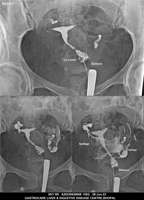

Section: HSG

Total: 49 Cases